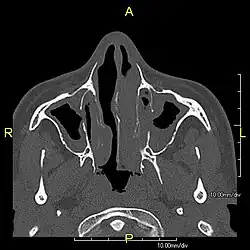

| Complications | Chronic recurrent respiratory infections, including sinusitis, bronchitis, pneumonia, and otitis media.[2] |

Around 80% of people with primary ciliary dyskinesia experience respiratory problems beginning within a day of birth. Many have a collapsed lobe of the lung and blood oxygen low enough to require treatment with supplemental oxygen.[1] Within the first few months of life, most develop a chronic mucus-producing cough and runny nose.[1] The main consequence of impaired ciliary function is reduced or absent mucus clearance from the lungs, and susceptibility to chronic recurrent respiratory infections, including sinusitis, bronchitis, pneumonia, and otitis media. Progressive damage to the respiratory system is common, including progressive bronchiectasis beginning in early childhood, and sinus disease (sometimes becoming severe in adults). However, diagnosis is often missed early in life despite the characteristic signs and symptoms.[2] In males, immotility of sperm can lead to infertility, although conception remains possible through the use of in vitro fertilization, there also are reported cases where sperm were able to move.[8] Trials have also shown that there is a marked reduction in fertility in females with Kartagener's syndrome due to dysfunction of the oviductal cilia.[9]

When accompanied by the combination of situs inversus (reversal of the internal organs), chronic sinusitis, and bronchiectasis, it is known as Kartagener syndrome[3] (only 50% of primary ciliary dyskinesia cases include situs inversus).[11]